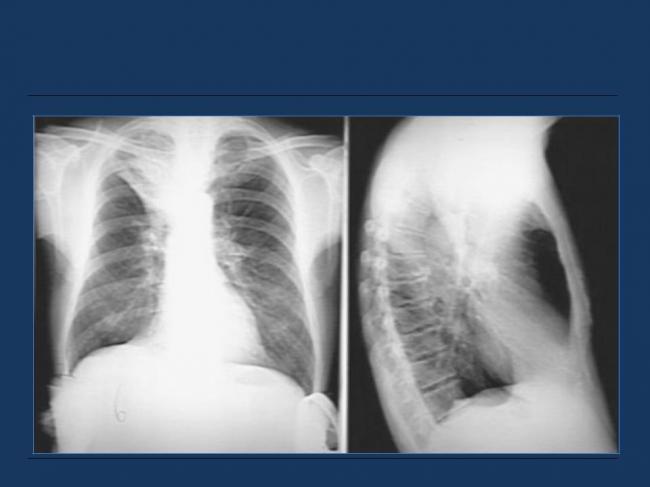

Помимо опроса и объективного осмотра, включающего перкуссию и аускультацию грудной клетки, проводят рентгенологическое исследование в двух положениях тела (в 2-х проекциях). Это основной метод обнаружения ателектазов легких.

На рентгеновских снимках выявляют следующие признаки, указывающие на спадение легочной ткани:

Однородное затемнение в области поражения. Размеры тени зависят от вида ателектаза: при долевом выявляется обширное затемнение, при сегментарном — в виде клина или треугольника, расположенного вершиной к корню легкого, дольковые ателектазы множественные и похожи на очаговую пневмонию. Дистензионный ателектаз расположен низко, около диафрагмы, имеет небольшие размеры и вид поперечных полос или темных дисков. Смещение органов: при компрессионном ателектазе смещение наблюдается в здоровую сторону, так как на стороне поражения давление больше, при обтурационном, наоборот – смещение будет в сторону ателектаза, так как на стороне поражения нарастает притягивающее отрицательное давление. Подъем купола диафрагмы – это видно по расположению печени.

Помимо всего перечисленного выше, рентгеноскопия, то есть исследование «вживую», позволяет увидеть куда смещаются органы в зависимости от фазы дыхания, кашля. Это является дополнительным признаком ателектаза, помогающим выявить тип болезни.

Если диагноз непонятен, рентгенологическое обследование дополняют компьютерной томографией. При перекрытии просвета бронхов выполняют бронхоскопию – осмотр по ходу бронхов с помощью зонда с камерой, который вводят в дыхательные пути.